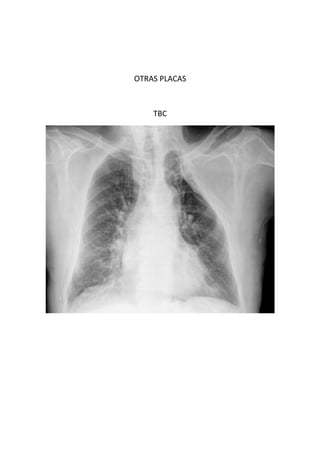

Este documento presenta 7 casos de patología torácica que serán discutidos en una sesión de interpretación radiológica. El objetivo es que los asistentes tomen notas aclaratorias durante la discusión interactiva de cada caso, en lugar de una mera explicación teórica. Los casos incluyen agenesia pulmonar derecha, situs inversus, estridor, neumonía con hemoptisis y enfermedad intersticial. El último caso involucra a un paciente de 86 años con tos y disnea que podría tener una consolidación en la base